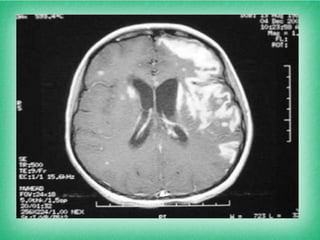

TAC- RNM CEREBRAL: hemorragias y reforzamientos

perivasculares, cambios difusos de la sustancia blanca,

granulomas, atrofia de la médula espinal y empiema.